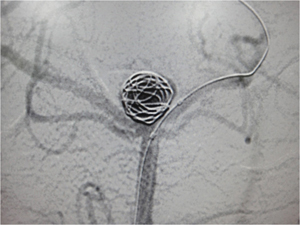

カテーテルを瘤内に誘導しコイルで塞栓しています。向かって右の血管(左後大脳動脈)に入っているのはバルーン(風船)カテーテルです。コイルがこちらの血管にふくらんでこないように助けています。

綺麗に塞栓されました。当初半昏睡であった患者さんですが、後遺症なく社会復帰されました。